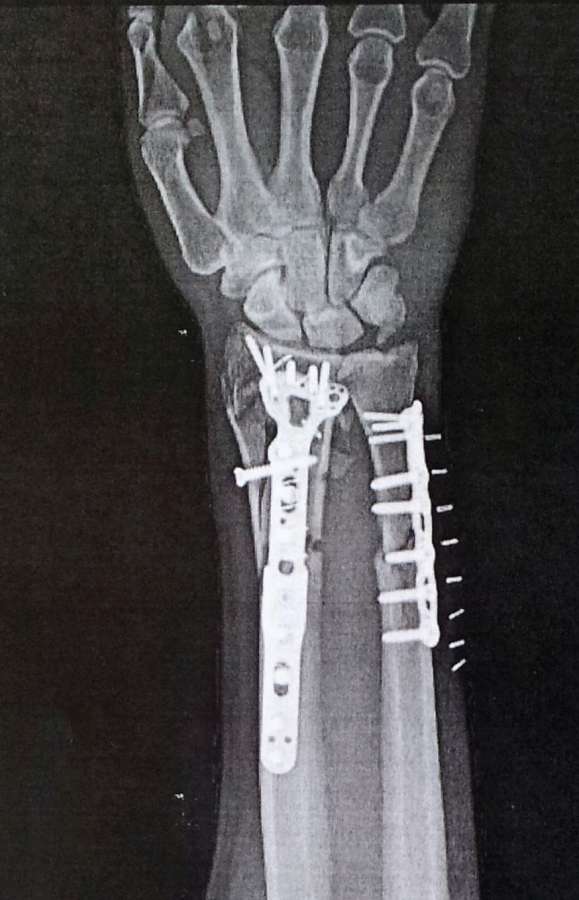

On November 7 I had an appointment with the doctor who repaired my hand. I was shocked to see the extent of the damage done to my arm. This was the first time I had seen it that I can remember. I believe that just as God has blessed in so many ways to restore my mind, He will heal my arm also. Please continue to pray for me. Your prayers mean so much to me. This is my right arm, and I am right handed. I use it to write Bible studies for Present Truth, so it is very important to me. Below is a picture of my hand, and the x-rays, all of which were taken on November 7. I appreciate all your prayers.

One of the most startling miracles of my injury is how God removed my pain. This is especially significant to me after seeing the x-rays of my arm. It is almost unbelievable what happened. My wife told me this story. It happened at a time when I cannot remember. It happened the first night of my injury, Sunday, October 20, 2013. My wife, Kendra, tells me that I was in excruciating pain, so much so that I pleaded with her to cut my arm off to get rid of the pain. Some of my friends who were there confirmed this report. I was not thinking very clearly, but I was certainly in a great deal of pain. The pain was so great Sunday night that I could not sleep. Finally, my wife prayed to God to remove my pain, quoting the verse in 1 Corinthians 10:13 that says, "There hath no temptation taken you but such as is common to man: but God is faithful, who will not suffer you to be tempted above that ye are able; but will with the temptation also make a way to escape, that ye may be able to bear it." Immediately, I became calm and went to sleep. I slept through the night and woke up the next morning with no pain. A nurse came in to administer pain medication. I asked what it was for. She said it would help get rid of the pain. I told her that I don't need it because I don't have any pain. She couldn't believe it and continued trying to give me pain medicine. I refused so she left me alone. Every so often the nurse would return to give me pain medicine. I refused it every time, and never complained about pain again for the next 11 days in the hospital. Monday evening, my second night in the hospital they brought me in to do surgery on my arm, as you can see above. They put me to sleep to do this invasive surgery. When I awoke there was still no pain. Again the doctors and nurses could not believe it. It is unheard of to endure such an invasive surgery with no pain. I continually refused pain medication every time they tried to give it to me. The only explanation I can come up with is that God removed the pain from me at my wife's request. What a great God we serve. This happened at a time when I was not in my right mind. I could not pray for myself. I thank God for answering the prayers of others on my behalf. Friends, take courage, nothing is too hard for God, and He is very concerned about every detail of your life.